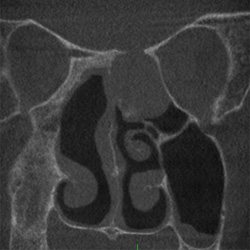

Hals-Nasen-Ohrenheilkunde

• Chronische Nasennebenhöhlenentzündungen

• Häufig wiederkehrende Nasennebenhöhlenentzündungen

• Polypen der Nasenhaupthöhle

• Unklare Gesichtsschmerzen

• Verdacht auf Fehlbildungen der Nase und der Ohren

• Chronische Mittelohrerkrankungen

• Unklare Hörverschlechterungen

• Verletzungen im Mittelgesicht

Chronisch polypöse Pansinusitis linksMukozele im linken Siebbein

mit Unterbrechung der Frontobasis